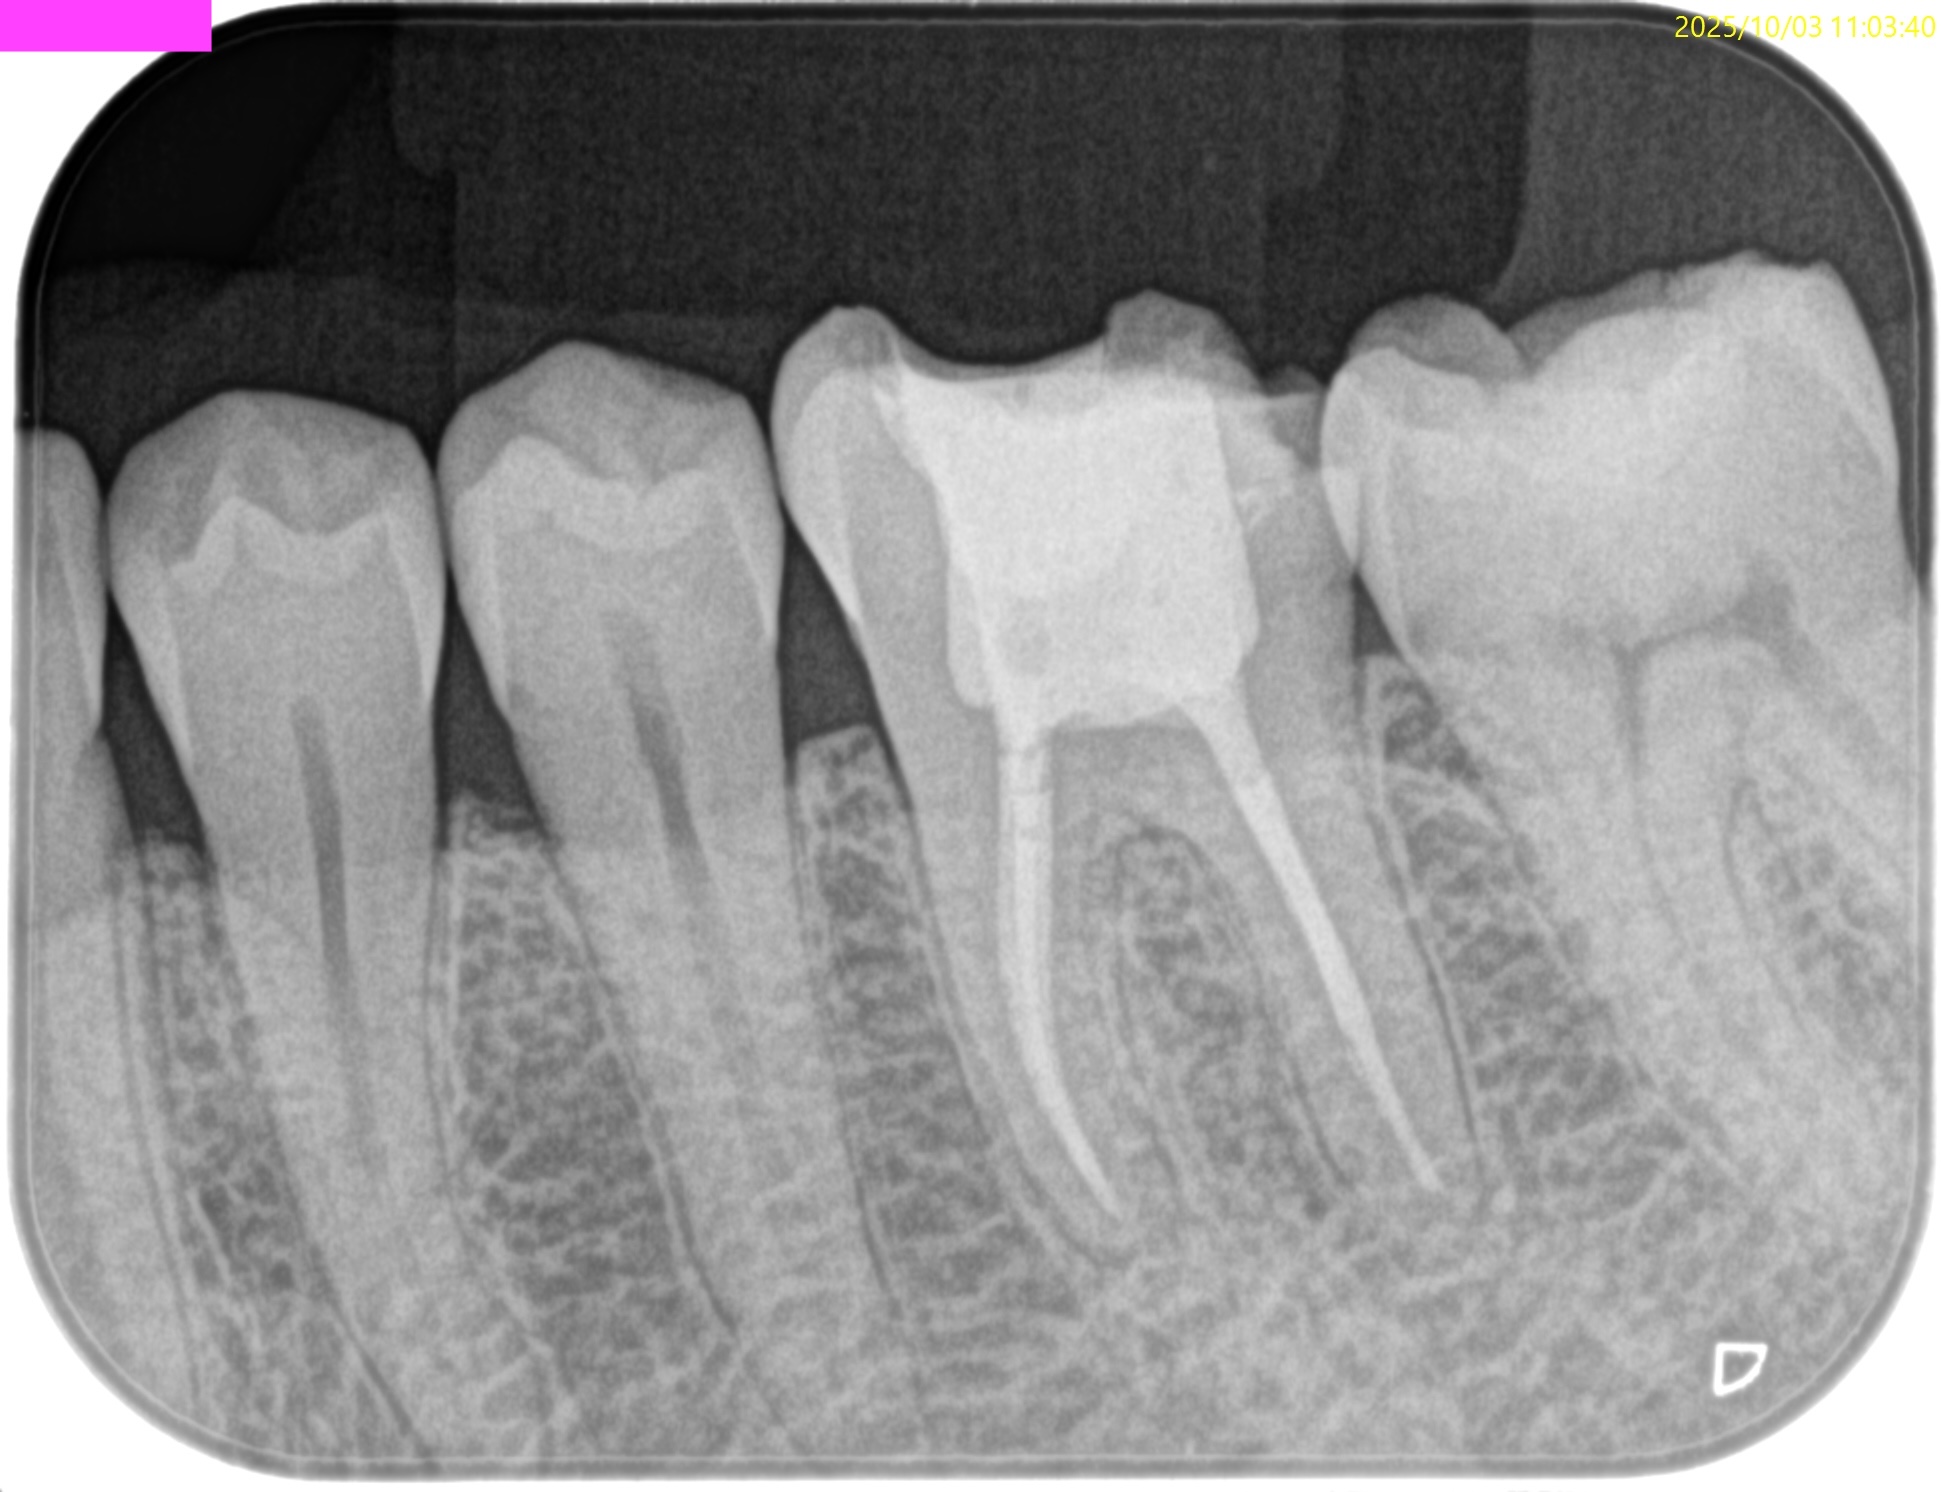

参考ケースは以下だ。

Dにはほぼ歯髄に修復物が覆いかかっている。

これは、

Asymptomatic irreversible pulpitisの可能性が高いだろう。